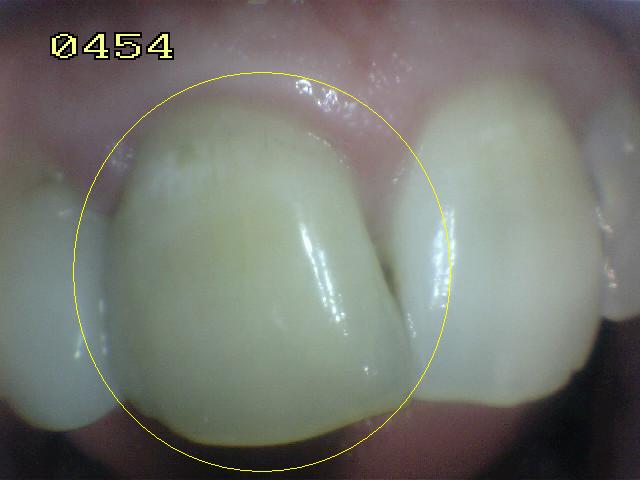

La tinción interna de la dentina por hemorragias intra-pulpares (traumatismos o biopulpectomias deficientes) puede decolorar los dientes de adentro hacia afuera. El blanqueamiento interno puede solucionar este problema.  Ver imagen derecha